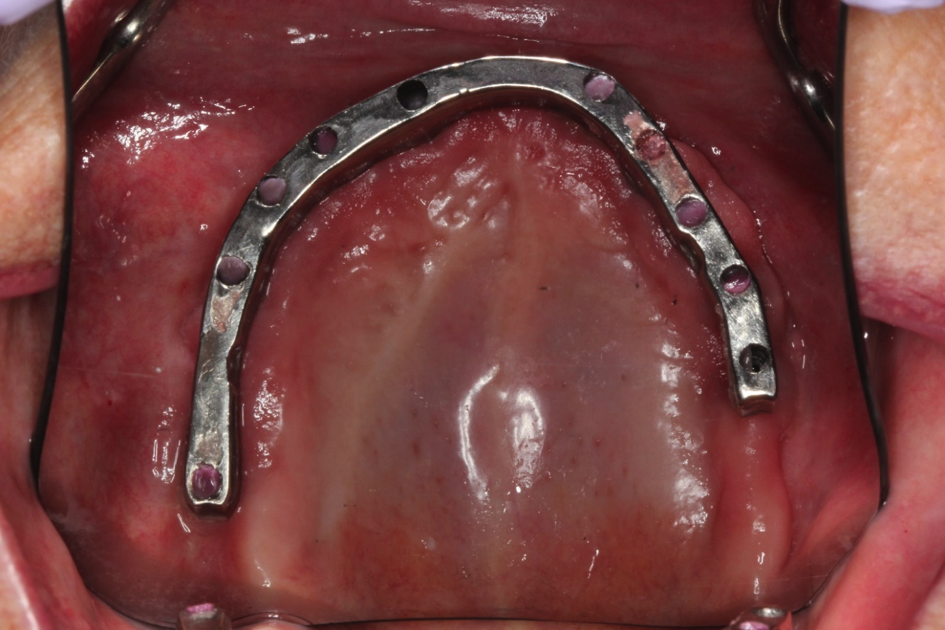

This patient came to us with a broken denture and bar. She wanted teeth that would make her smile again. We fabricated her a new bar that attached to her implants and placed teeth on them. This is a permanent bridge that is made of titanium and acrylic.